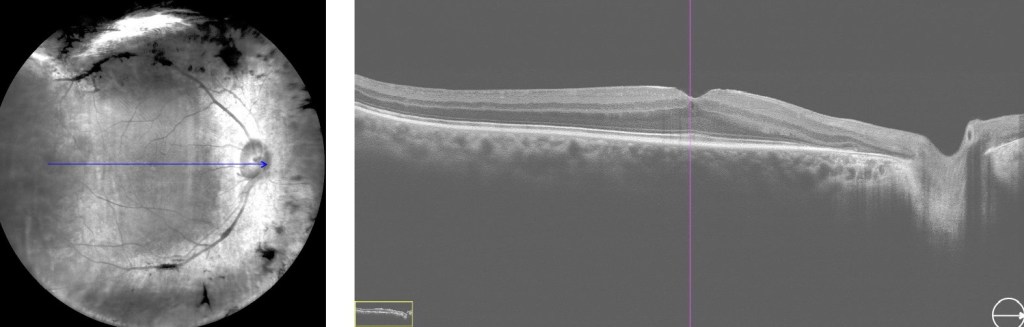

Je souhaite vous partager un cas très intéressant de chirurgie chez un patient atteint de rétinopathie diabétique sévère. Un homme de 63 ans, diabétique, présentait une cataracte modérée et une baisse progressive de la vision, réduite à la perception des doigts. Malgré un traitement clinique antérieur, la maladie avait continué de progresser. Il avait été soumis à des examens du fond d’œil, à une angiographie à la fluorescéine et à une tomographie par cohérence optique.

La procédure a débuté par l’extraction de la cataracte, suivie d’une vitrectomie standard par pars plana, réalisée à travers trois orifices avec un calibre de 23. Une prolifération fibrovasculaire dense a été observée au niveau de la zone maculaire. Une pince crantée de calibre 25 a été utilisée pour engager et soulever le tissu fibreux, qui a été pelé en bloc. Deux échanges air-fluide ont été effectués au cours de l’intervention.